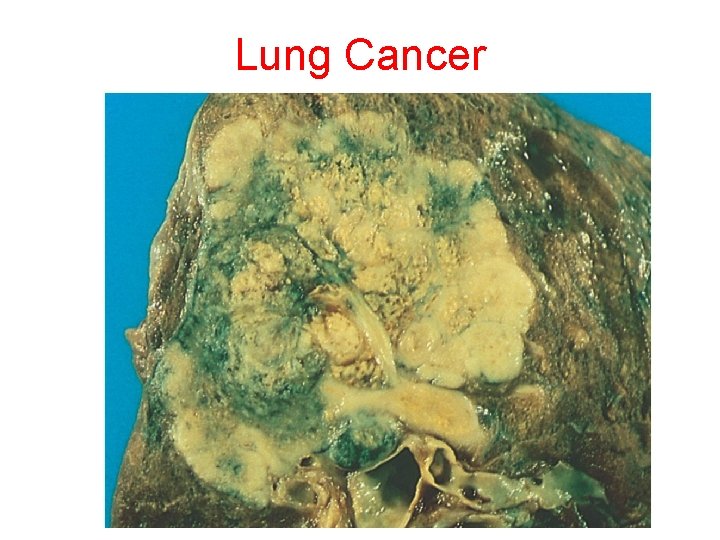

Lung Cancer